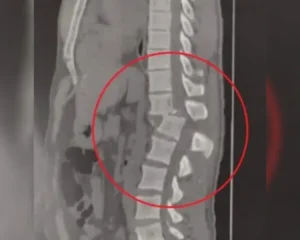

Em qualquer acidente com impacto na coluna, o diagnóstico rápido é vital. Os principais exames são:- Tomografia Computadorizada: Essencial para avaliar a gravidade das fraturas ósseas com rapidez.